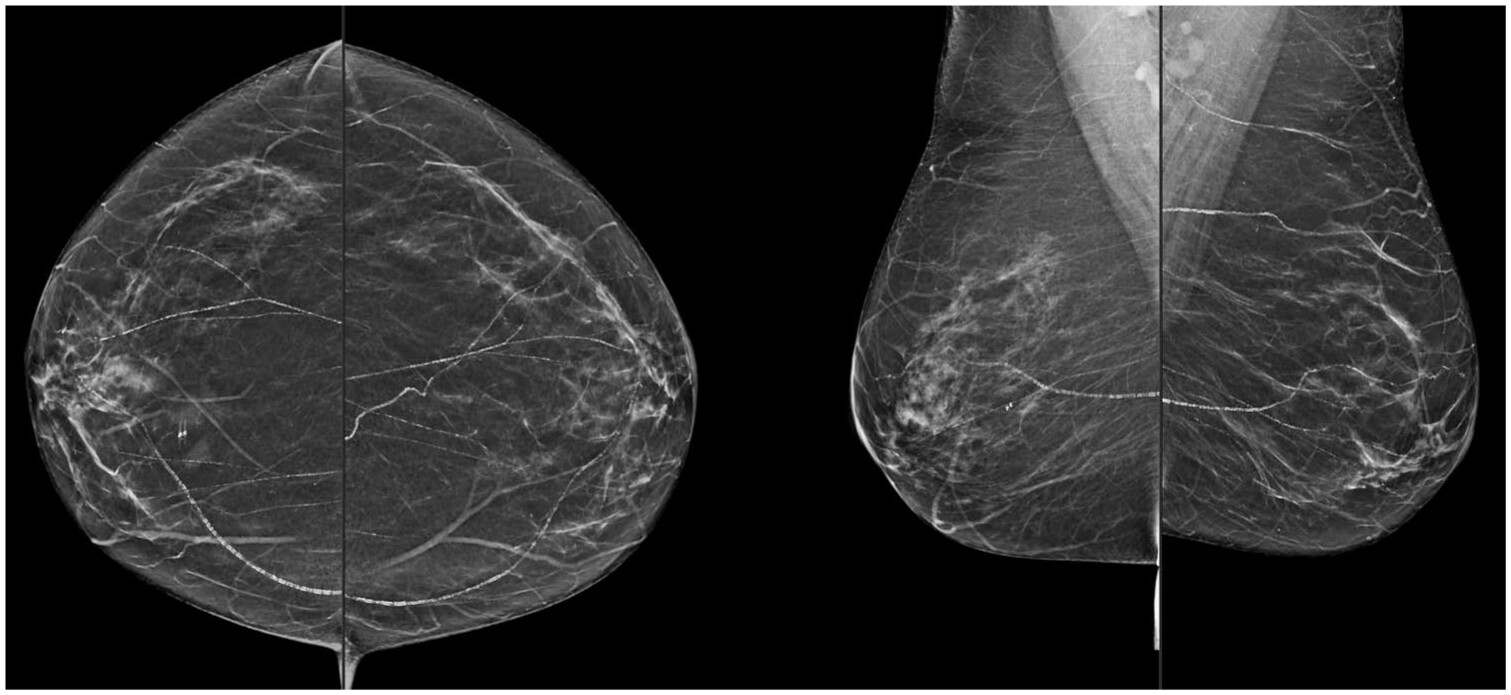

The detection and quantification of BAC on mammography can be performed subjectively by the interpreting radiologist. Depending on their severity, BAC may appear as coarse, tram-track, or tubular calcifications on mammography (Figure 1).16,38 BAC are often clearly distinguishable from other benign and suspicious microcalcifications by their morphology and proximity to breast vasculature. While BAC reporting is not required based on the American College of Radiology (ACR) Breast Imaging Reporting and Database System (BI-RADS) 5th edition guidelines, radiologists may choose to describe vascular calcifications when reporting mammography.53

Figure 1. Craniocaudal and mediolateral oblique 2D synthetic mammographic images of a 67-year-old female presenting for routine screening demonstrating severe bilateral breast arterial calcifications.